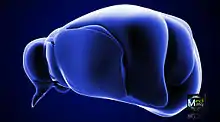

Thalamus markeret (MRI-scanning)

Anterolateral vinkel